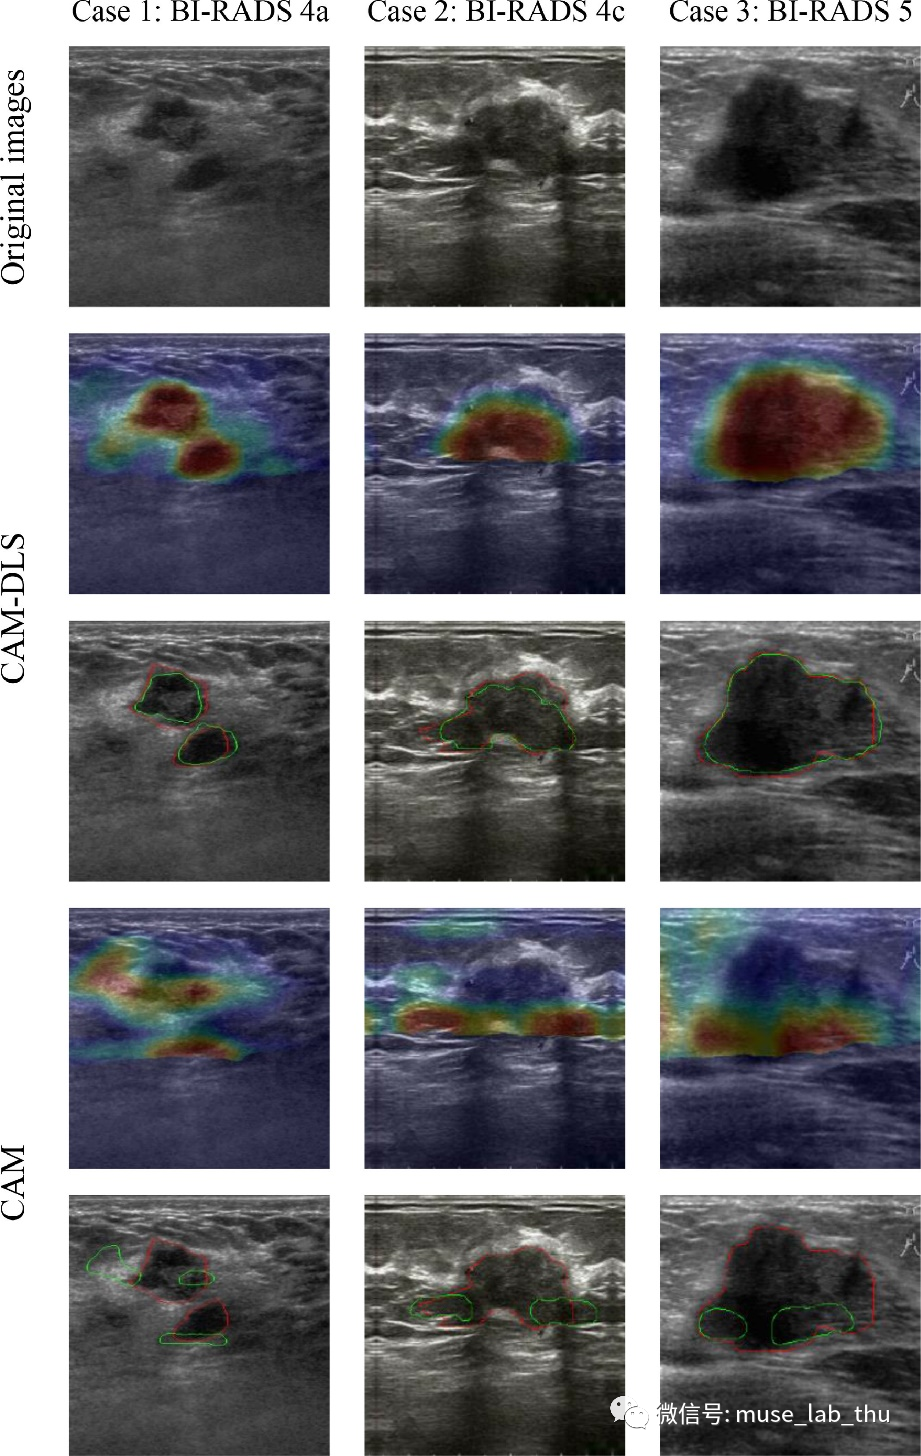

实验结果表明:DLS损失的加入,大幅度提高了CAMs的定位精度(如图2所示);在测试集上,CAM-DLS方法的Dice系数为77.3%,交并比(IoU)为66.0%,该弱监督学习分割方法的效果接近甚至优于现有的半监督学习分割方法;对BI-RADS 3类、4类和5类的乳腺肿瘤,CAM-DLS方法均能准确分割出肿瘤边界(如图2所示)。

图2 部分测试集结果